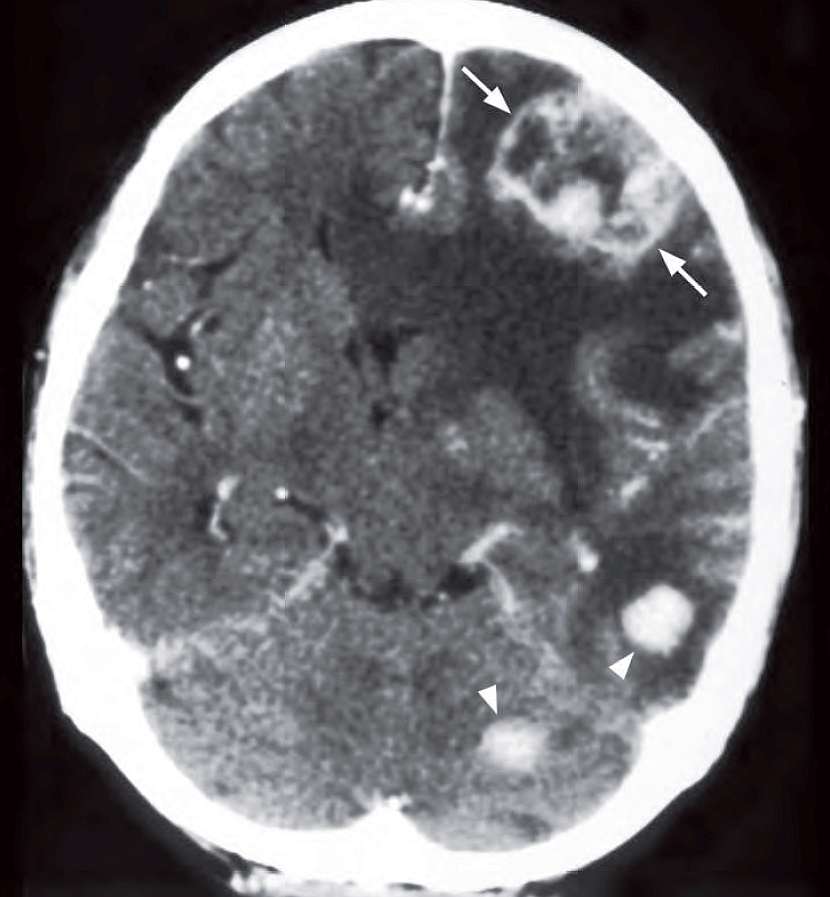

A 77-year-old woman had carcinoma of the left breast resected 2 years earlier. Her relatives noticed that she had become increasingly clumsy with progressive memory loss in the last 2 months. A contrast enhanced CT brain was performed.

What is shown on the CT and what is the most likely diagnosis ?